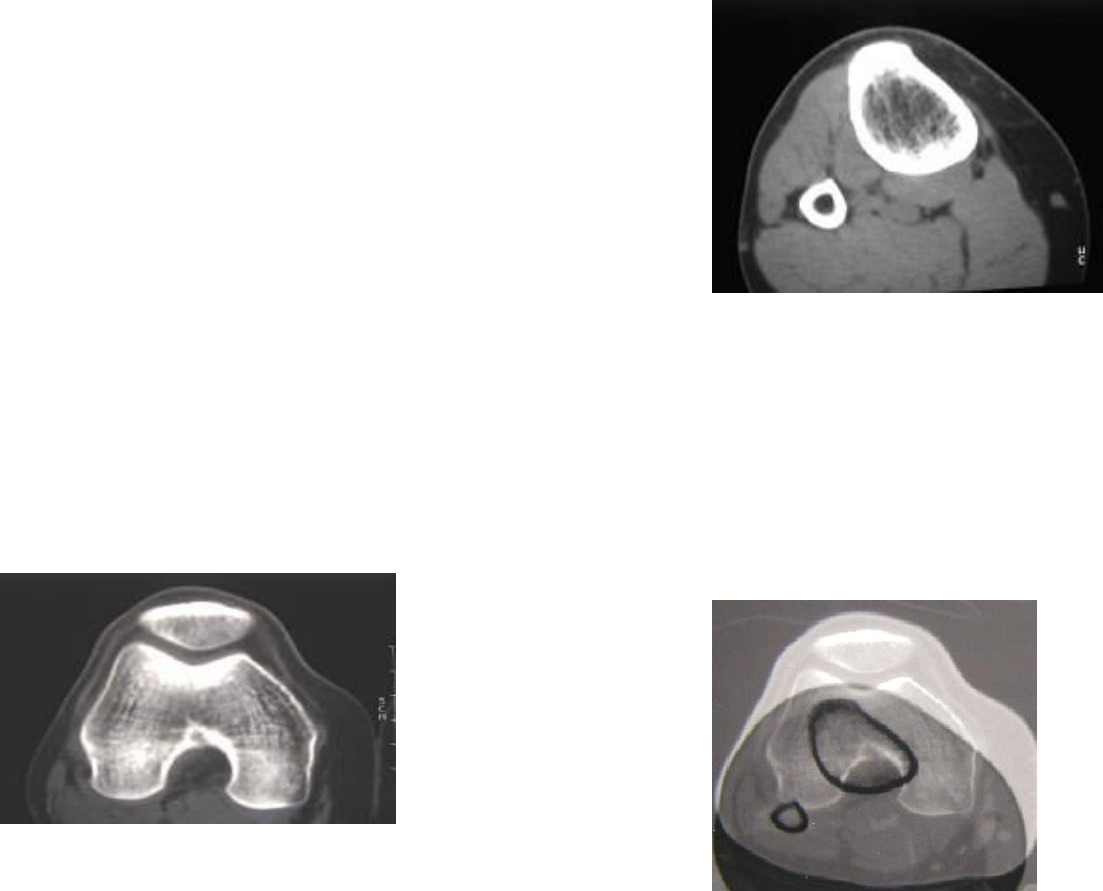

A medida TA-GT é a representação da distância entre o vértice do sulco da tróclea femoral e a tuberosidade anterior da tibia. Um dos fatores predisponentes da instabilidade femoro-patelar é o aumento da lateralização da tuberosidade tibial.

Para a execução destas medições, o paciente é posicionado para realizar um TC aos joelhos em que os mesmos são colocados em extensão completa ( 0 graus ) e com uma flexão de 30 graus.

Realização das medições TA – GT (TA - tuberosidade anterior da tíbia) (GT - garganta da troclear).)

1º) Escolher duas imagens adquiridas no TC realizado anteriormente.

Imagem do terço distal do fémur.

Imagem do terço proximal da tíbia.

OBS: ( deve visualizar-se bem os dois côndilos femorais e definir-se bem a GT ) / ( deve visualizar-se bem a TA)

2ª ) Somar as imagens (sobrepor as imagens)

3º) Desenhar as retas que permitem medir TA-GT.

-Traçar uma reta que passe tangencialmente p/ bordas posteriores dos dois côndilos femorais - (1)

-Traçar uma reta perpendicular à anterior que passe pela GT - (2)

-Traçar uma reta perpendicular à anterior que vai unir à TA - (3)

OBS: O valor obtido em (3) é a distância entre TA e GT que só é considerado como patológico se for superior a 20mm com os joelhos em extensão completa (0 graus) e inferior a 4mm ou superior a 14mm com os joelhos flectidos a 30 graus.